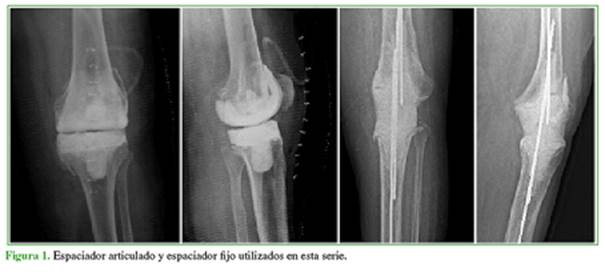

En la actualidad, la cirugía en dos tiempos para tratar la infección periprotésica articular colocando un espaciador de cemento cargado con antibiótico antes del reimplante de la prótesis es el tratamiento más utilizado y la tasa de erradicación de la infección es >80-90%.2 Los espaciadores de cemento con antibiótico se pueden clasificar en dos tipos: fijos, que no permiten la movilidad articular de la rodilla y articulados, que mantienen cierto rango de movilidad durante su uso (Figura 1).

La confección de los espaciadores ha ido evolucionando y permanentemente se analizan las ventajas y desventajas de estos dos tipos de espaciadores. Las tasas de erradicación de la infección son similares independientemente del tipo de espaciador. Hoy se recomienda más el uso de espaciadores articulados sobre la base de una teórica mejoría de la movilidad articular.3-5